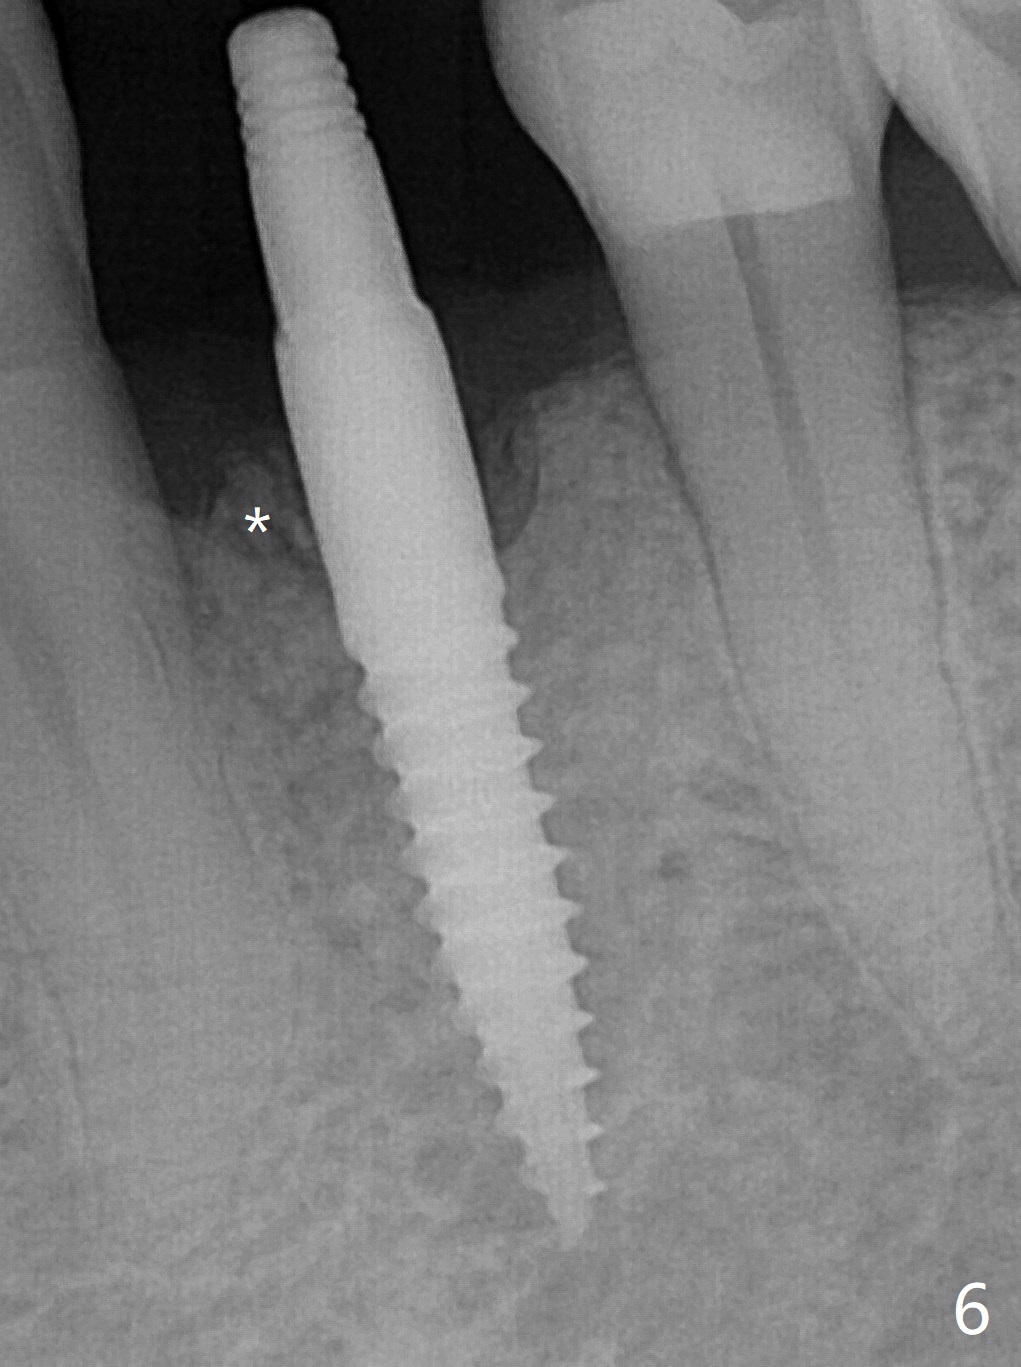

After incision at #21 (Fig.1) and flap elevation, the narrow ridge is reduced and initial osteotomy is made (Fig.2,3). Following moving the osteotomy distal, a 3x12(4) mm 1-piece implant is placed with >35 Ncm (Fig.4-6). Vanilla Graft is placed in the most concave buccal defect (Fig.1,4 *) and over the ridge reduction area (Fig.6 *). No bone loss is observed 3 months postop (Fig.7).